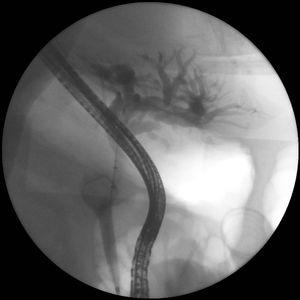

Mujer de 70 años que ingresa por colecistitis aguda y coledocolitiasis con deterioro clínico a las 12h por shock séptico secundario a colangitis. Se solicita CPRE urgente en la que se detecta dilatación de vía biliar proximal secundaria a compresión por un cálculo de2cm enclavada en cístico (fig. 1). Dada la situación clínica se implanta una prótesis plástica doble pig-tail para aliviar la obstrucción biliar (fig. 2), realizando colecistectomía parcial y cierre sobre tubo Kehr con extracción de la litiasis a los 11 días tras mejoría del estado de la paciente.